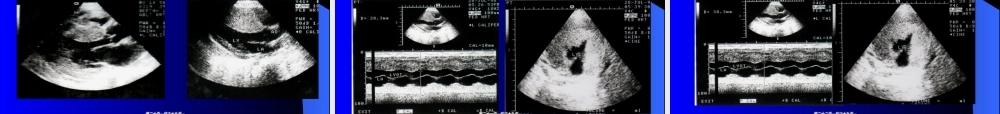

原发性心肌病原发性心肌病心肌病是指病变主要在心肌的一类心肌病。除外高血压性、冠状动脉性、瓣膜性、肺原性和先天性心脏病所致的心脏病变按照病理(bìnglǐ)及血流动力学特征分为三型:(1)扩张型心肌病;(2)肥厚型心肌病;(3)限制型心肌病。心肌病是指病变主要在心肌的一类心肌病。除外高血压性、冠状动脉性、瓣膜性、肺原性和先天性心脏病所致的心脏病变按照病理(bìnglǐ)及血流动力学特征分为三型:(1)扩张型心肌病;(2)肥厚型心肌病;(3)限制型心肌病。第一页,共六十九页。第一页,共六十九页。DilatedCardiomyopathyyDilatedCardiomyopathyy第二页,共六十九页。第二页,共六十九页。不明(bùmín)ɡ原因的左右或两侧心室扩张伴收缩功能受损应除外冠心病,结绨组织病,内分泌,药物等引起的继发性心肌病不明(bùmín)ɡ原因的左右或两侧心室扩张伴收缩功能受损应除外冠心病,结绨组织病,内分泌,药物等引起的继发性心肌病第三页,共六十九页。第三页,共六十九页。ClicktoaddTitle扩张型心肌病以左室扩大或右室扩大或全心扩大为特征,并伴有心力衰竭(xīnlìshuāijié)。由于心室扩大,房室环也因而增大,常引起房室瓣关闭不全。约占心肌病的70%。第四页,共六十九页。第四页,共六十九页。第五页,共六十九页。第五页,共六十九页。第六页,共六十九页。第六页,共六十九页。扩张型心肌病病理解剖与血流动力学心脏普遍扩大,心肌松软,由于心肌广泛变性坏死,间质结缔组织增生,心肌收缩力减弱,心脏泵功能衰竭(shuāijié).由于心脏扩大,常引起房室瓣关闭不全.第七页,共六十九页。第七页,共六十九页。充血性心力衰竭心律失常栓塞左室扩大X线:心胸(xīnxiōng)比例>0.50-0.55心室造影:LVEF<40%-45%LVEDVI>80ml/m2充血性心力衰竭心律失常栓塞左室扩大X线:心胸(xīnxiōng)比例>0.50-0.55心室造影:LVEF<40%-45%LVEDVI>80ml/m2第八页,共六十九页。第八页,共六十九页。扩张型心肌病超声诊断要点(yàodiǎn)1.心室扩大,左室为著2.室壁运动普遍减低3.房室瓣开放减小第九页,共六十九页。第九页,共六十九页。室壁运动室壁运动(yùndòng)(yùndòng)普遍减弱普遍减弱扩张性心肌病扩张性心肌病第十页,共六十九页。第十页,共六十九页。4、M型超声显示二尖瓣前叶舒张期活动幅度降低(jiàngdī),瓣口开放小,呈“钻石样”改变,与扩张的心腔对比显大心腔小瓣口的特点。第十一页,共六十九页。第十...